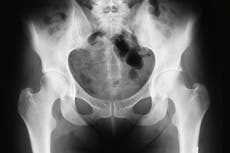

McMinn made his name after inventing a new type of hip surgery that was used by doctors to salvage the tennis career of Sir Andy Murray.